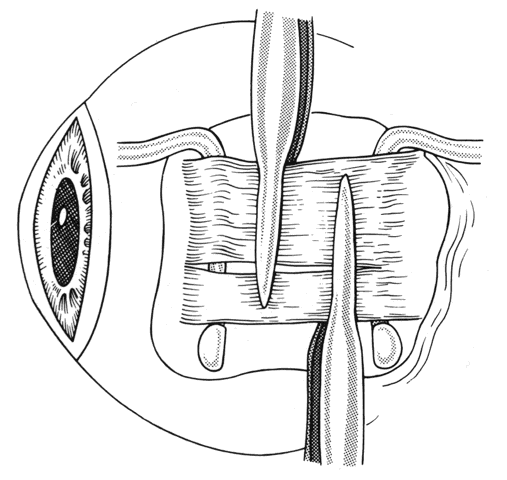

The insertion of a previously operated rectus muscle may have anterior extensions of scar tissue or even a pseudotendon. The term pseudotendon refers to fibrous tissue that extends from the surface of the true tendon (Fig. 26). If a muscle has been previously recessed, these attachments may extend anterior and become adherent to the original insertion. Care must be taken to identify “pseudotendons” and to separate them from the true tendon of the rectus muscle (Figs. 27 through 29).

Fig. 26. Care must be taken to identify the true insertion. A fibrous extension from the insertion can extend anterior to the old or original insertion. This is called a “pseudotendon” because it may simulate the tendon of the rectus muscle inserting on the globe. Inset. A Stevens hook is under a “pseudotendon.” The true tendon is posterior to this fibrous structure.

Fig. 27. After identification of the insertion of the true tendon of the rectus muscle, the “pseudotendon” is excised with sharp dissection. Dissection should be carried down to bare sclera.caption.

Fig. 28. This intraoperative photograph demonstrates tissue that may simulate the insertion of the lateral rectus muscle. The cornea is to the right, just visible under the lid. The Jameson hook is under tissue that extends from the original insertion and the inferior oblique muscle. The true insertion is further posterior. The insertion of the muscle was found to be 17.5 mm posterior to the limbus.

Fig. 29. Attachments can occur between sclera and the rectus muscle. These need to be cut or disrupted. Failure to do this will alter the desired effects of recession or resection of the rectus muscles.